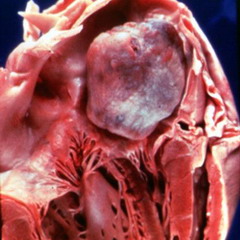

Миксома — доброкачественная опухоль неправильной формыМиксома является опухолью доброкачественного характера, которая имеет желеобразное содержимое и неправильную форму. Наиболее часто у пациентов встречаются миксомы сердца.

По внешнему виду миксома сердца представляет собой образование в виде полипа с желеобразным содержимым. Данная опухоль располагается на предсердной перегородке и в размерах достигает до 12-15 см.

В основном, миксома предсердия располагается в левой части, где получает кровь от легких. Опухоль может располагаться возле митрального клапана и препятствовать току крови из предсердия в желудочек. Периодически миксома то раскрывает, то закрывает отверстие клапана, нарушая кровоток.